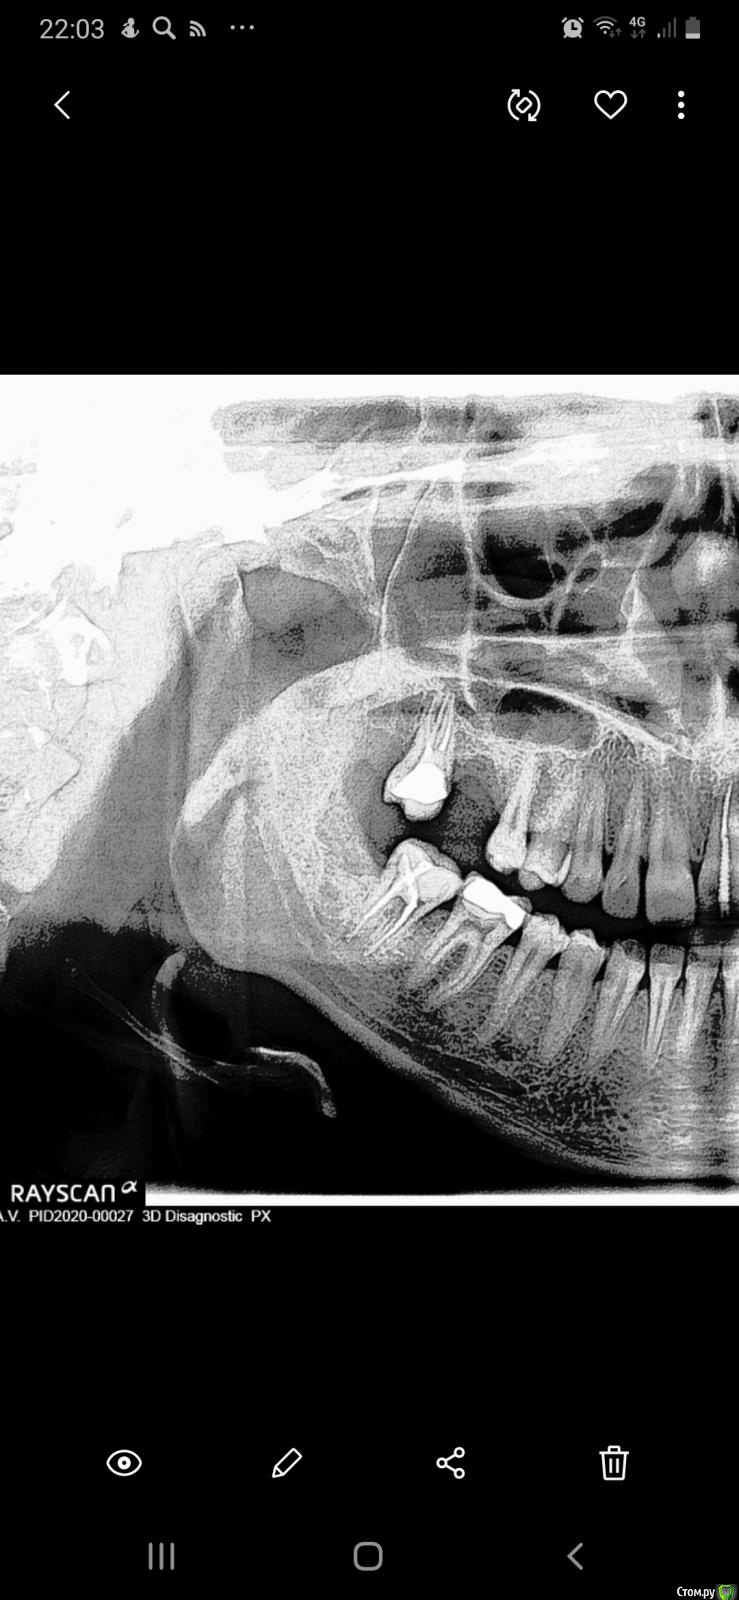

Kartohka Опубликовано 10 января, 2020 Автор Поделиться Опубликовано 10 января, 2020 Вот снимок Ссылка на комментарий

Kartohka Опубликовано 10 января, 2020 Поделиться Опубликовано 10 января, 2020 Добрый вечер)Уже месяц беспокоят боли в десне справа 7 нижнего зуба, болит в области десны при нажатии и при постукивании, чувство жжения и буд-то иголки вставляют под десну, плюс поясился дискомфорт между 4 и 5 зубом нижним, при открытии рта и зевании дискомфорт у 5 зуба, при соприкосновении с щекой, чувство что под десной инородный предмет, вырвали зуб номер 8 пару мпсяцев назад ,при этом подвывихнули челюсть Ссылка на комментарий